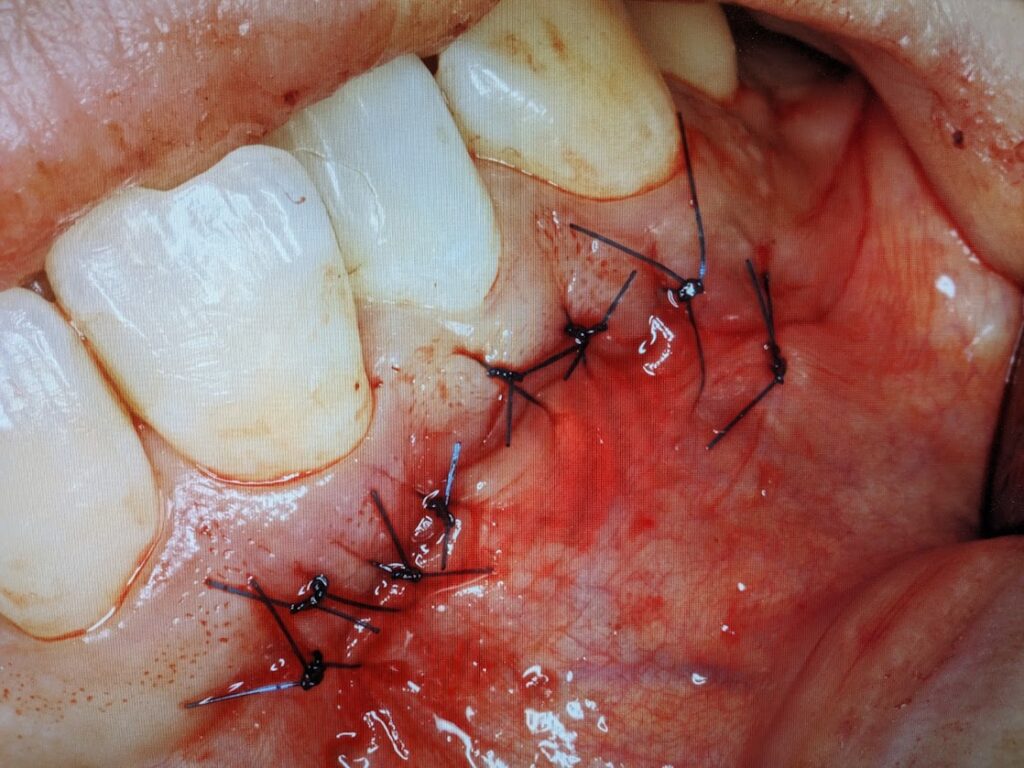

縫合処置を実施して手術は終了です。現在経過観察中です。